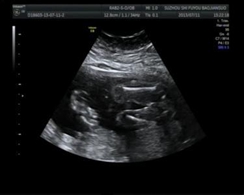

医学影像学可以作为一种医疗辅助手段用于诊断和治疗,也可彩超

彩超(3张)

以作为一种科研手段用于生命科学的研究中。诊断主要包括透视、放射线片、CT、MRI、超声、数字减影、血管造影等。治疗主要应用为介入治疗、放疗等方面。